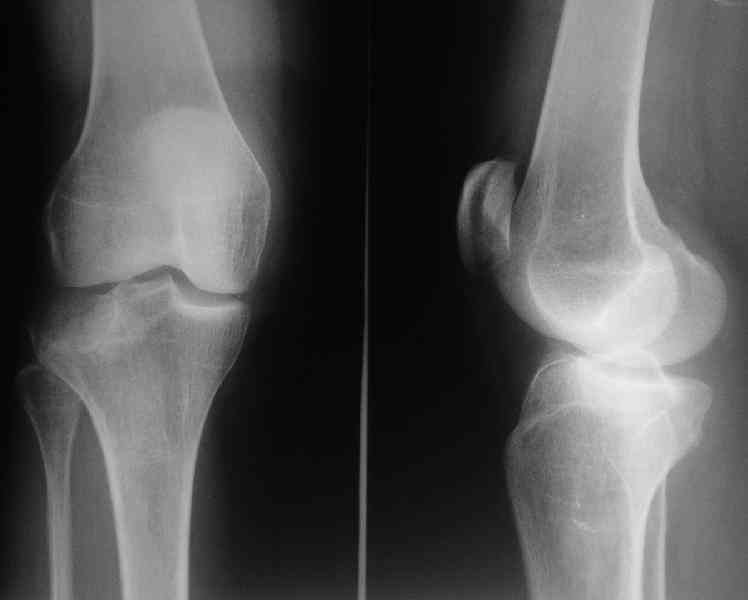

Здравствуйте, уважаемые коллеги!Подскажите, пожалуйста, какой выбрать доступ и способ фиксации при импрессионном переломе заднего отдела наружного мыщелка большеберцовой кости. Женщина 40 лет, травму получила 02.01.2008, катаясь на горных лыжах.Есть ли здесь необходимость использовать задний доступ, или можно справиться через наружный? Есть ли шансы сделать закрыто - под ЭОП через медиальное "окошко" поднять забойником суставную поврехность? Какой лучше использовать фиксатор?Спасибо.

центральная импрессия, а при ипрессии с краевым переломом - после приподнимания импрессии опорная (Butress) пластина, как на снимке.